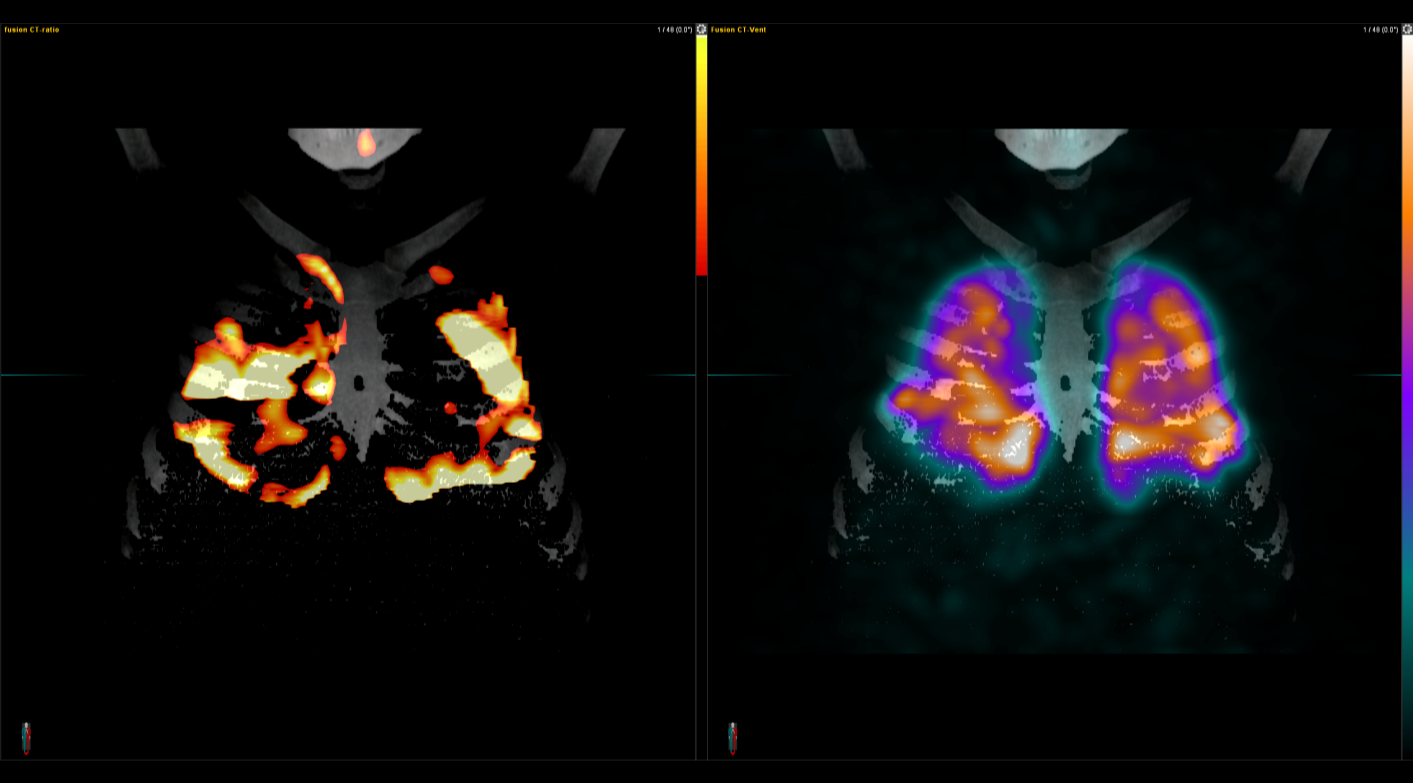

IQ SPECT Η τέχνη της ελαχιστοποίησης της δόσης με ταυτόχρονη μεγιστοποίηση της ταχύτητας Στη σύγχρονη Πυρηνική Ιατρική, όπου η ανάγκη για ταχύτερες και ασφαλέστερες μελέτες Μυοκαρδιακής Αιμάτωσης (MPI) αυξάνεται διαρκώς, το IQ SPECT αποτελεί μία από τις πλέον ώριμες και καινοτόμες τεχνολογίες. Η αρχή του είναι απλή και καθαρή: να συλλέγει όσο το δυνατόν περισσότερα δεδομένα από την καρδιά, με την ελάχιστη δυνατή δόση και στον ελάχιστο χρόνο, χωρίς συμβιβασμούς στην ποιότητα εικόνας. Minimum dose & maximum speed Στις συμβατικές SPECT καρδιάς, μεγάλο τμήμα του ανιχνευτή δεν αξιοποιείται λόγω του μικρού μεγέθους του εξεταζόμενου οργάνου. Αυτό οδηγεί σε παρατεταμένο acquisition – πολλές φορές έως 16 λεπτά – ώστε να εξασφαλιστεί η αναγκαία ποιότητα εικόνας. Το IQ SPECT υπερβαίνει αυτόν τον περιορισμό. Με βελτιστοποιημένο χειρισμό της γεωμετρίας, των collimators και του acquisition, μεγιστοποιεί τα ανιχνευόμενα δεδομένα από την καρδιά, επιτρέποντας ολοκληρωμένη μελέτη σε λιγότερο από 5 λεπτά, μείωση της χορηγούμενης δόσης έως και 75%, και διατήρηση ή και βελτίωση της ποιότητας εικόνας.

Οι μελέτες μυοκαρδίου πραγματοποιούνται με τη χρήση της μοναδικής τεχνολογίας IQ SPECT που εξασφαλίζει μικρό χρόνο απεικόνισης – μικρή δόση – υψηλή διακριτική ικανότητα/ανάλυση.